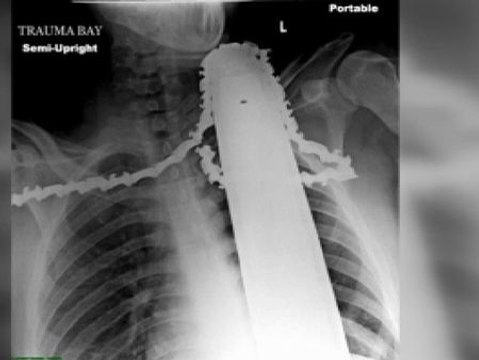

Kira tiene 19 años y es todo un ejemplo de superación. Lleva cantando desde que tenía 6 y hace unos meses le descubrieron un tumor cerebal que podría impedirle volver a hacerlo. Pero en el hospital infantil de Seattle no pensaban permitirlo, así que la operaron al ritmo de la música que ella cantaba. Con el cerebro abierto, sin dolor, sin molestias, pero despierta. Los cirujanos querían asegurarse de que Kira pudiese seguir dedicándose a su pasión y así ha sido porque cantaba tan solo 48 horas después de la operación. Guitarra en mano y dando a todos una lección de vida.  -Redaccón-